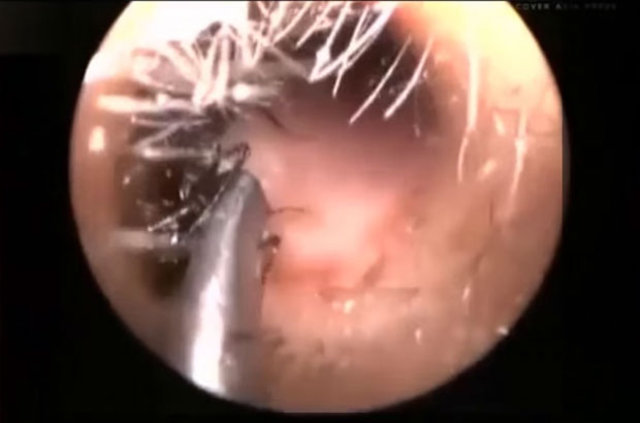

Endoskopik kamerayla çekilen görüntülerde doktorlar Shreya'nın kulağından, ölü karıncalar çıkarıyor. Küçük kızın çaresiz anne ve babası her yolu denediklerini ancak karıncalardan kurtulamadıklarını dile getirdiler.

Kulak Burun Boğaz Hastalıkları Uzmanı Dr. Jawahar Talsania, "Yapılabilecek tüm taramaları yaptık. MRI ve CT taramalarına rağmen her şey normal görünüyor. Küçük Shreya'nın kulaklarında hiçbir anormallik bulamadık.

Karıncaların bazen ısırmaları dışında küçük kız hiçbir acı çekmiyor. Kulak kanallarında herhangi bir hasar da tespit etmedik" açıklamasında bulundu.